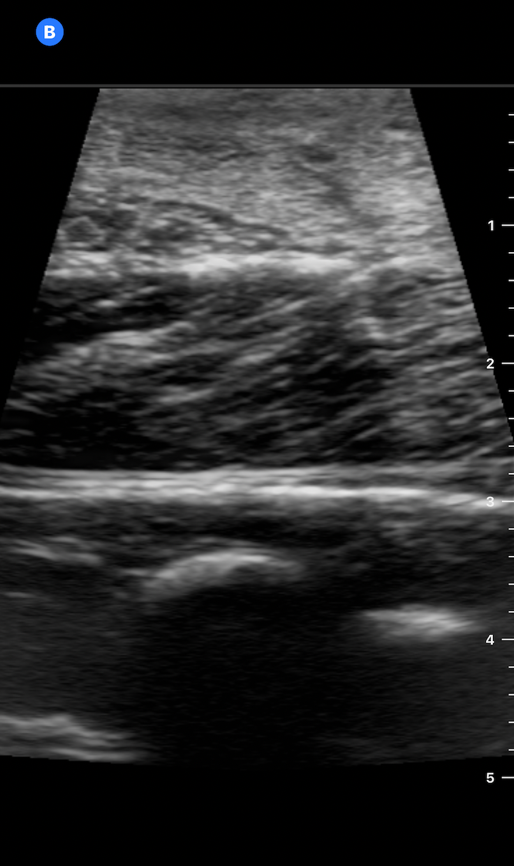

We found that the polenta appeared denser on POCUS than the tofu block, but the string cheese appeared similar to the tofu block, and the needle was easy to visualize in-plane. (Image 6) An injection was performed, and while it did not significantly affect visualization of structures on the phantom, it also did not show significant hydrodissection.

NerveBlock-Image6 Aug2024.pngImage 6. Polenta medium on POCUS with in-plane visualization of needle